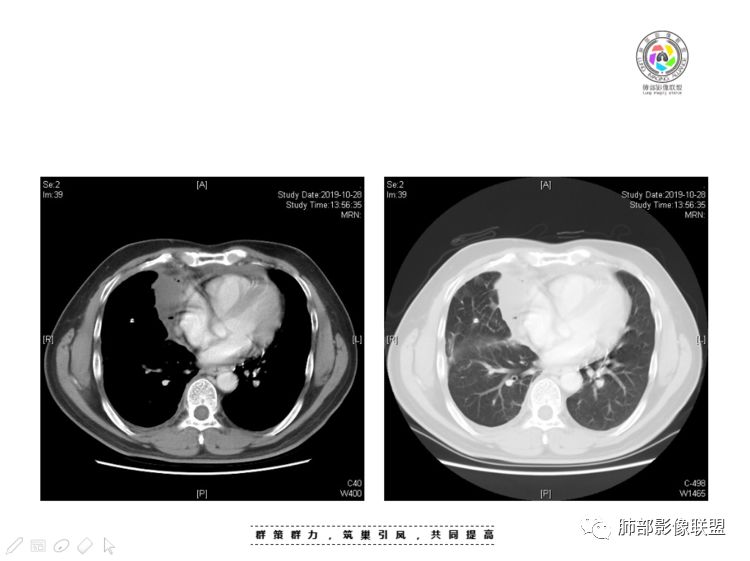

穿越七海的风:右前纵隔占位,恶性肿瘤,生殖来源?右肺实变是占位or肺不张?考虑为部分肺不张FeNo:右前纵隔占位,右肺结节,胸膜凹陷,小尾巴,右肺不张,考虑恶性杨旭华:恶性,前纵隔肿物,与血管关系密切,上腔静脉变窄,右肺野一元论考虑叶间裂增厚,恶性胸膜间皮瘤可能大小丽:到底是纵隔来源还是胸膜来源?我怎么倾向于胸膜来源,和叶间胸膜关系密切,而且纵隔内上腔静脉是向内侧推移。胸膜肿瘤(间皮瘤?SFT?)包裹性胸腔积液?马春平(张家港市一院胸外科):前纵隔占位,左无名受压,右大量胸腔积液可能是胸导管汇入处侵犯受压,考虑纵隔鳞癌孙冰伟:右上纵隔占位,也感觉和叶间胸膜关系密切,右侧胸膜局限性增厚,考虑恶性可能性大灵:前纵隔占位,血性胸水,胸膜凹凸不平,查见肿瘤细胞,结合免疫组化考虑胸腺癌。鉴别胸膜间皮瘤。采莲:右前上纵膈旁可见类圆形肿块,纵隔血管内移,感觉来源于胸膜,肿块内密度低,似水样密度,右侧胸膜广泛增厚,少量胸腔积液。心包少量积液。考虑胸膜间皮瘤,鉴别肺癌并胸膜转移?水晶石头:患者中年男性,胸闷15天。有“高血压、慢性肾小球肾炎”病史。查肿瘤标志物正常,胸水提示渗出液,胸水病理查见瘤细胞。胸部CT:右肺上叶后段结节、斑片影,见胸膜牵拉、包裹积液及部分纤维条索灶,似见卫星灶,右侧胸膜增厚。前纵隔脂肪密度增厚,右侧可见类圆形低密度(液体)肿块,边缘光滑。综合考虑右肺腺癌并胸膜转移,结核可能。周太狼:考虑纵隔胸膜来源肿瘤,恶性,胸膜间皮瘤伴转移?徐飞:中年男性,影像为右侧胸腔及叶间积液,叶间胸膜增厚轻度强化。前纵隔右侧心缘旁团块,可见坏死。胸水见癌细胞,综合考虑恶性,胸腺癌伴转移。小赵:中年男性,血性胸水,常规查见癌细胞,李凡他实验阳性。胸部CT示前纵隔见不均匀密度影,与邻近大血管分界不清,囊变坏死明显,增强扫描呈不均匀强化,心包及右侧胸膜增厚,并心包及右侧胸腔少量积液。综合考虑胸腺癌。右肺中叶病变周围见多发纤维条索,支气管部分进入病灶,考虑炎性病变。流心明智:患者,男性,50岁。胸闷15天。高血压20年,慢性肾小球肾炎15年。肿标正常,胸水提示渗出液,胸水查见癌细胞。胸部CT:右肺肿块影,斑片影,索条影,可见胸膜牵拉、多发包裹积液,纵隔上腔静脉受累,心包受累。综合考虑:ROSE似腺?考虑右肺腺癌并胸膜转移,心包受累。鉴别胸腺Ca、淋巴瘤,纵隔病变不懂,等老师们精彩分析。王秀仙:前纵膈囊实性肿块,与纵膈分界不清,心脏大血管及上腔静脉受压向内后移,右侧后胸膜、侧胸膜增厚,右侧叶间裂不规则增厚,心包积液,根据腔静脉移位情况,考虑纵膈胸膜来源恶性肿瘤,胸膜间皮瘤?鉴别胸腺癌并胸膜转移。高广飞:上纵隔占位,右侧叶间胸腔积液,需考虑恶性自信人生:多发囊实性病灶,包裹性积液,考虑胸膜来源 只是没有看到壁结节,恶性胸膜间皮瘤巴伟:前上纵隔占位,胸膜及心包结节,考虑胸腺瘤或癌,右肺病灶,先考虑陈旧炎性病变。Lenle董:前纵隔占位,部分边缘模糊,病灶内囊变?坏死?上腔静脉受侵,考虑胸腺癌;叶间片状影,强化明显,炎性考虑。常志强:前纵隔囊实混杂密度肿块,边界不清,实性部分强化明显,结合胸水内见癌细胞,考虑恶性肿瘤伴转移。飞鹰行动:前纵隔占位,软组织密度及囊性密度,实性部分密度均匀,致密,病灶与周围血管分界不清,增强后病灶强化有类似不温不火强化,部分血管受侵犯,右肺见肿块样病变及条索状病变,一元论,考虑淋巴瘤,二元论,考虑胸腺瘤B2—B3伴右肺病变。尽量一元论考虑,淋巴瘤可能。看图说话:右肺索条病灶,边缘膨隆,胸膜牵拉,考虑右肺癌伴胸膜转移。晨:前纵隔囊实性肿块,与纵隔分界不清,右侧后胸膜、侧胸膜增厚,右侧叶间裂不规则增厚,考虑纵隔胸膜来源恶性肿瘤,考虑胸腺癌并胸膜转移。丽:中年男性,前纵隔囊实性肿块,呈偏心性生长,临近大血管受压推移,增强后实性部分不均匀强化,心包可见条形积液,考虑胸膜来源恶性肿瘤,胸腺癌可能大。另右肺多发斑片状高密度影及实变密度影,实变影呈均匀强化,右侧胸膜局限性增厚,考虑炎性病变。小飞:右前纵隔囊实性占位,实性部分明显强化,右侧叶间胸膜增厚,右侧胸腔积液,心包积液,考虑恶性胸腺瘤!尘缘:支持恶性胸腺瘤(囊实性肿块,实性强化,且侵犯纵隔,脂肪间隙模糊)伴肺内及胸膜转移。浪迹天涯:考虑侵袭性胸腺瘤——胸腺前纵隔占位,周围脂肪间隙模糊不清。尘缘:不除外另一种可能:二元,肺内腺癌合并胸膜转移,纵隔的畸胎瘤可能。一米阳光:晨读中年男性,右肺结节影,叶间裂及胸膜增厚牵拉,右侧胸水。心包多发结节改变。胸水查见癌细胞。考虑,腺癌并转移。鉴别,胸膜间皮瘤并转移前纵隔囊实性占位,二元考虑。心灵鸡汤:老年男性,右肺中叶外段长条状软组织密度影,边缘膨隆,邻近胸膜牵拉,部分胸膜有栽脏,右中叶外侧段支气管堵塞,常规考虑恶性肿瘤,腺癌可能,结核、鳞癌不除外,另右肺上叶斑片影,小叶性肺不张?右前纵隔囊实性不规则形密度影,其内见部分脂肪样极低密度影,与邻近血管边界不清,心包外膜有侵犯,增强未见纵隔窗平扫,实性及分隔见增化,其内低密度影未强化,考虑低度恶性纵隔肿瘤,间皮瘤可能,畸胎瘤、淋巴瘤待排,建议支气管镜及穿刺活检。曹志勇:右前纵隔考虑来源于胸膜的恶性肿瘤,右肺内病灶考虑鳞癌,二元德芙~云味:中年男性,右肺见结节、斑片影,右侧包裹积液、胸膜牵拉,纤维条索,前纵隔囊性占位,考虑腺癌、并转移。欧阳英:右前中纵隔囊实性肿块及右肺内结节灶,支持恶性肿瘤,胸腺癌并肺内转移可能张延军:前纵隔见不规则软组织影,密度不均,右侧缘见囊变区,纵膈及侧胸壁胸膜增厚,增强呈不均匀强化,右肺中叶见结节灶,近段支气管阻塞,叶间胸膜不规则增厚,考虑1:右肺中叶腺癌伴纵膈及胸膜转移;2:前纵膈侵袭性胸腺瘤并胸膜侵犯,中叶炎性改变?彭君:老年,前纵隔占位 ,坏死边缘清, 侵犯心包 右侧胸膜及叶间胸膜结节 ,少量胸水, cea不高 ,考虑恶性, 间皮瘤可能 ,转移待除外。毛勤香:恶性没问题,胸水查见癌细胞,一元还是2元,右肺中叶肿块,边缘毛糙,局部似有毛刺,周围有粘连,右侧胸膜腔少量积液,胸膜增厚多发结节,含叶间裂结节,纵膈脂肪间隙模糊,纵膈胸膜增厚,心包增厚积液,右前那个类圆形低密度肿块,纵膈血管内移,我考虑胸膜来源可能性大,综合考虑,一元肺腺癌并多发转移,二元考虑胸膜间皮瘤并多发转移,肺内炎症不张。

1、右肺内病灶,病灶呈结节样,边缘欠规则,局部膨隆,叶间裂胸膜牵拉凹陷,再看相应支气管腔堵塞截断,临床资料胸水中查到癌细胞,均提示病灶倾向恶性,腺癌的病理意见与之相吻合。

黄勇老师总结,腺癌如果与胸膜、叶间裂紧贴或伴胸膜凹陷,胸膜、叶间裂多发结节,应当高度怀疑腺癌转移。

2、前纵隔内病灶囊实性混杂密度病灶,囊性病灶主要位于右侧,张力较高,有分隔影,囊壁右侧缘光整,病灶左侧实性部分边界不清明显强化,病灶肺瘤交界面大部分边界清楚,部分模糊。

胸腺瘤/胸腺癌:病灶内那么大的囊,常规考虑B型以上胸腺瘤,囊内有分隔影,病灶周围脂肪间隙模糊,常规考虑侵袭性胸腺瘤或胸腺癌,若侵袭性胸腺瘤,常侵犯胸膜、心包,很少累及肺。胸腺癌易侵犯胸膜、肺并纵隔淋巴结及远处转移。但肺内腺癌形态更符合原发灶。胸膜及叶间裂转移则即可来自肺,也可来自胸腺癌。